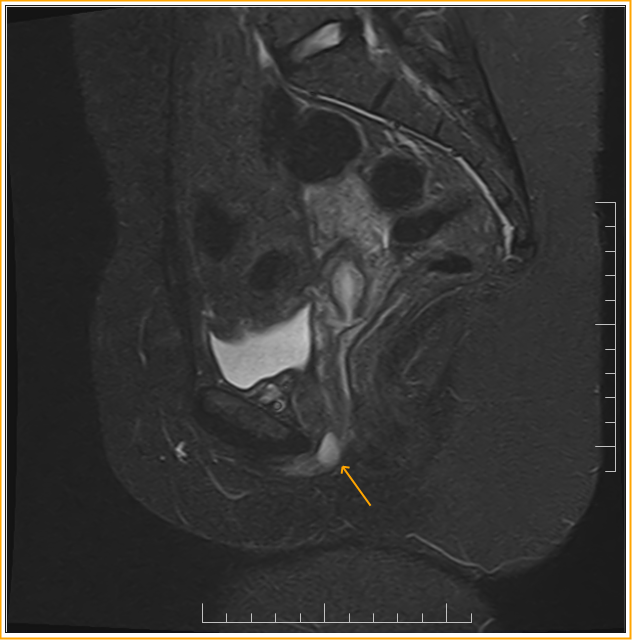

From www.researchgate.net

MRI picture illustrating a urethral diverticulum Download Scientific What Is A Urethral Diverticulum Urethral diverticula, or urethroceles, are focal outpouchings of the urethra. Urethral diverticulum (ud) is a condition in which a variably sized “pocket” or outpouching forms next to the urethra. A urethral diverticula is described as a cystic structure that is adjacent to the urethra. What is a urethral diverticulum? They should not be confused with a ureterocele of the distal. What Is A Urethral Diverticulum.

Urethral diverticulum (female prostate sign). Sagittal fast spinecho What Is A Urethral Diverticulum The diagnosis and management of urethral diverticula (ud) present a challenge to the reconstructive urologist. They should not be confused with a ureterocele of the distal ureter. It is thought to arise. A urethral diverticula is described as a cystic structure that is adjacent to the urethra. What is a urethral diverticulum? Urethral diverticulum (ud) is a condition in which. What Is A Urethral Diverticulum.